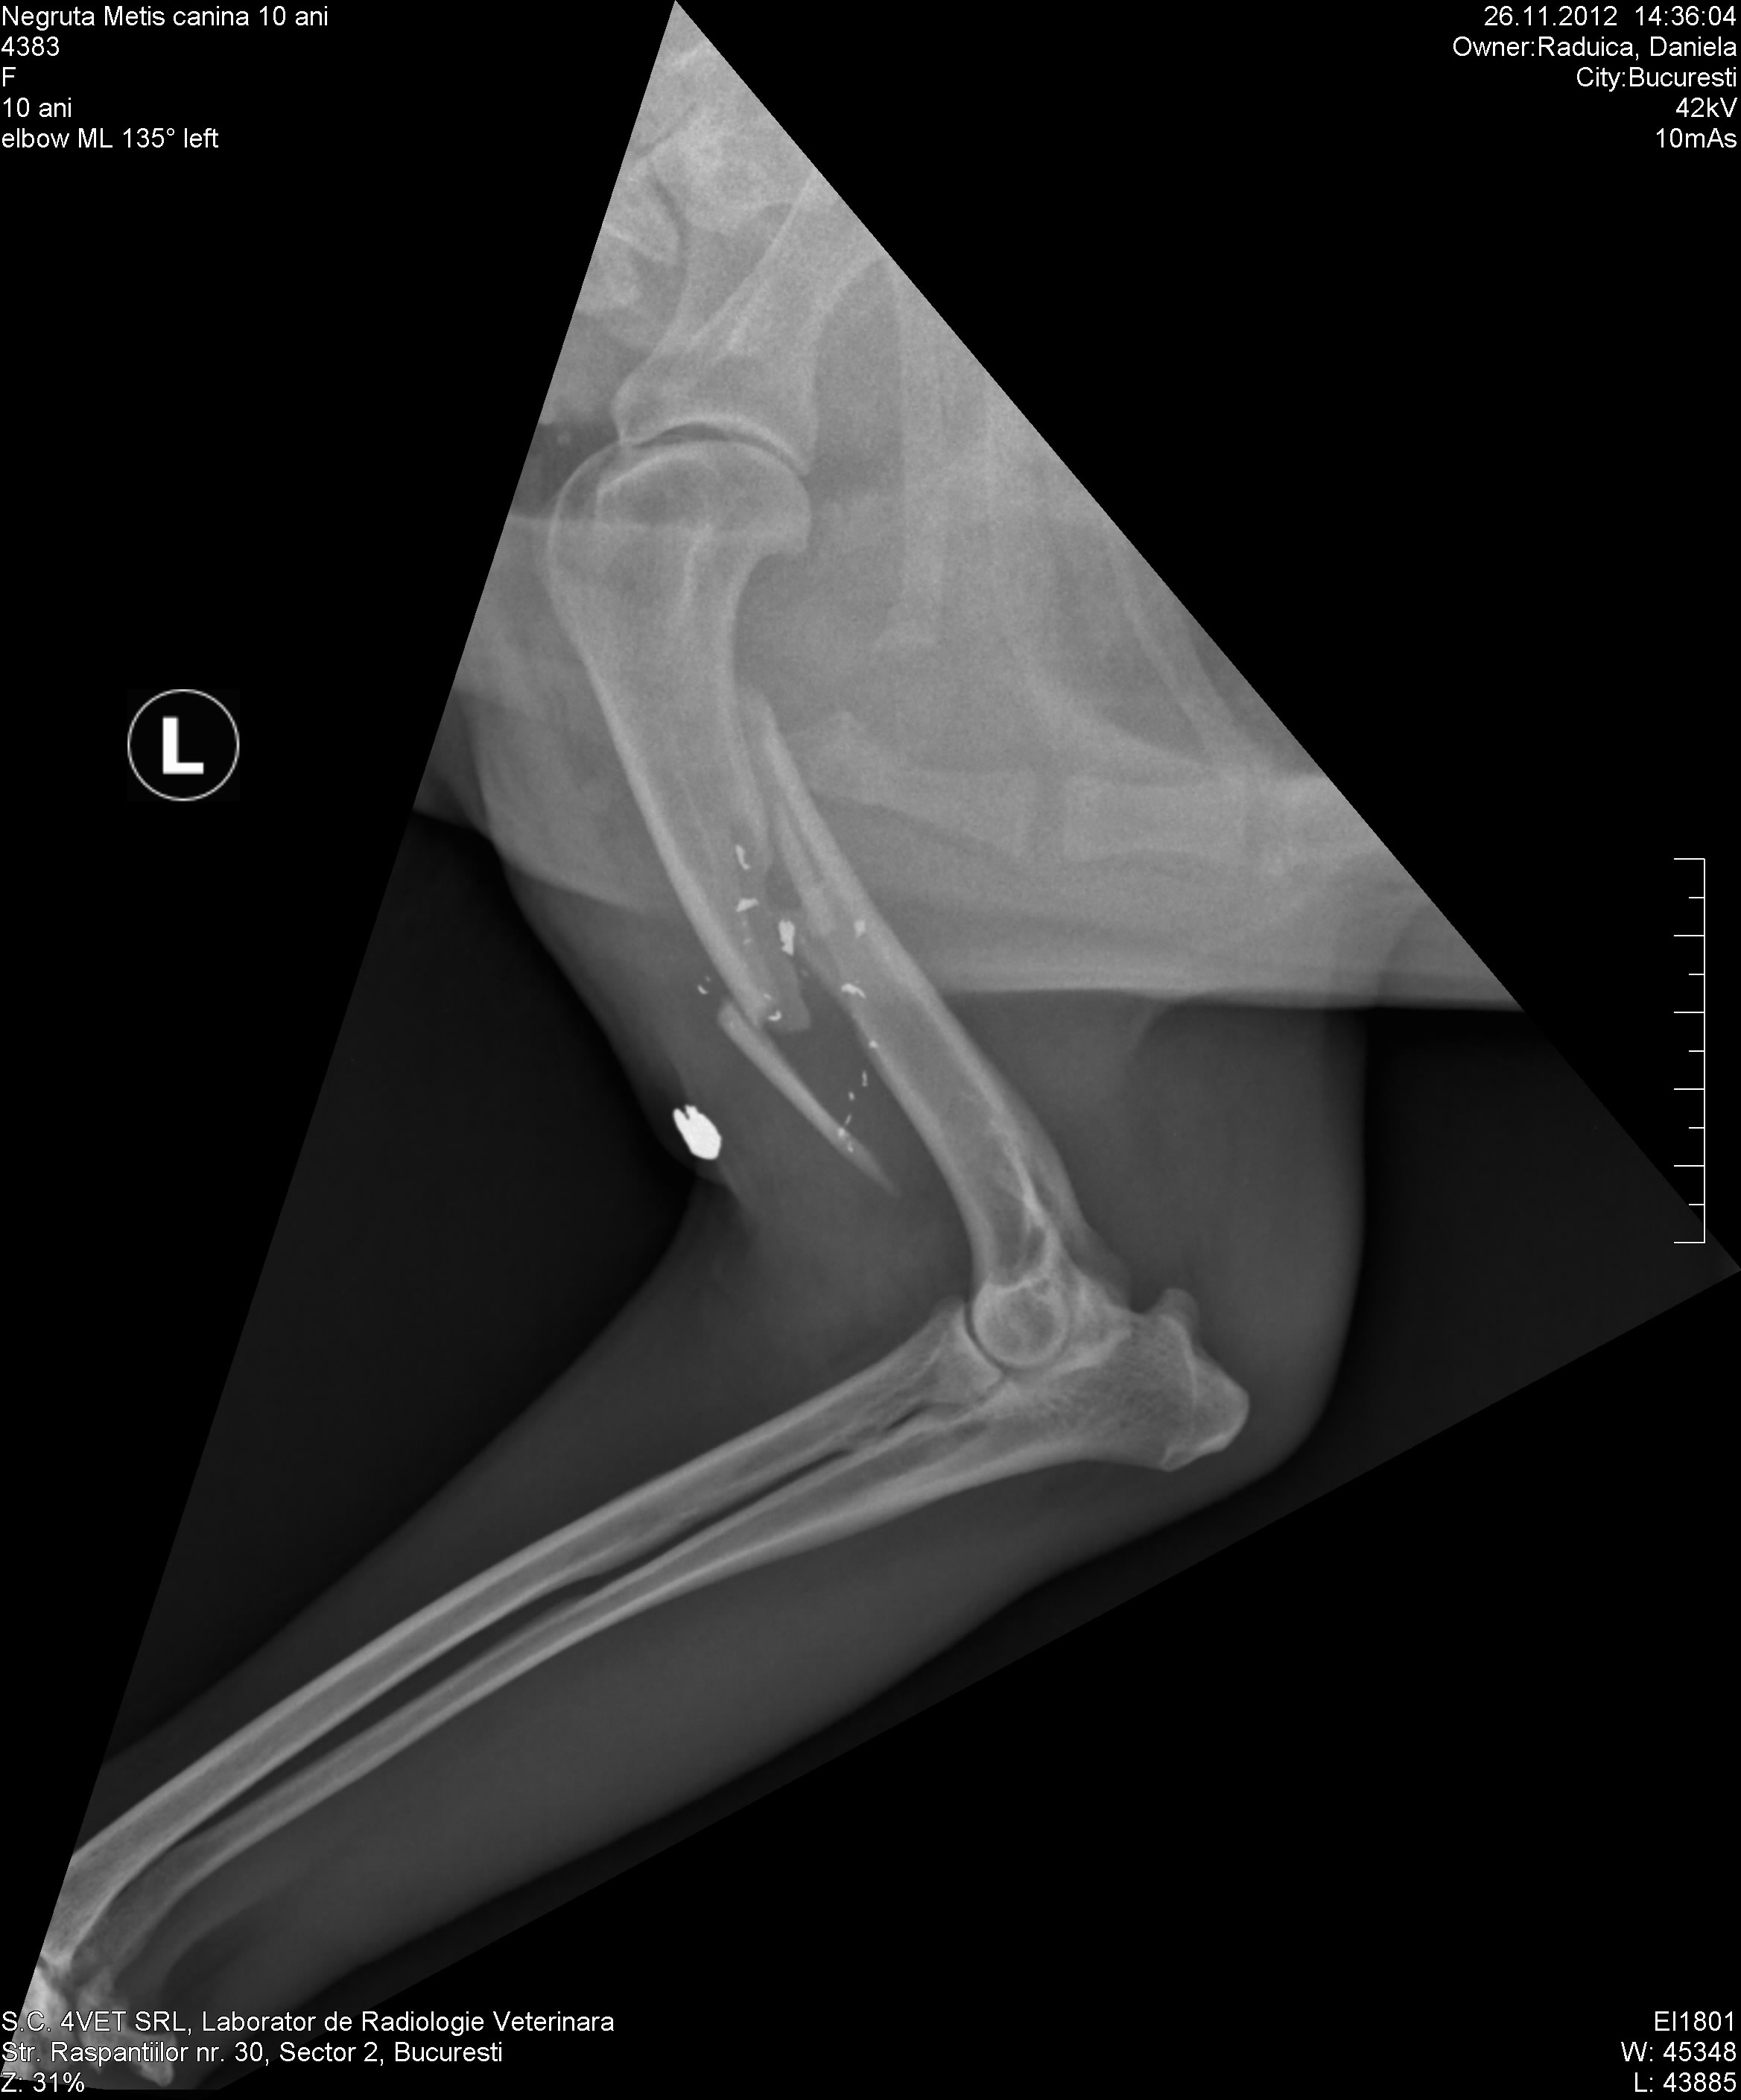

“Nu-mi revin din soc! Mi-am gasit animalele impuscate in curtea casei, in zile diferite. Am mers cu ele la veterinar si, potrivit radiografiei, arata ca au fost impuscate! Am facut o cercetare sa vad cine ar fi in stare de asa ceva, si am aflat ca un vecin care sta vizavi de mine ar fi facut asta. Cu atat mai mult cu cat, spun unii, ar mai fi impuscat pana acum si pisicile ori cainii altor vecini”, a declarat cantareata pentru CANCAN.ro.